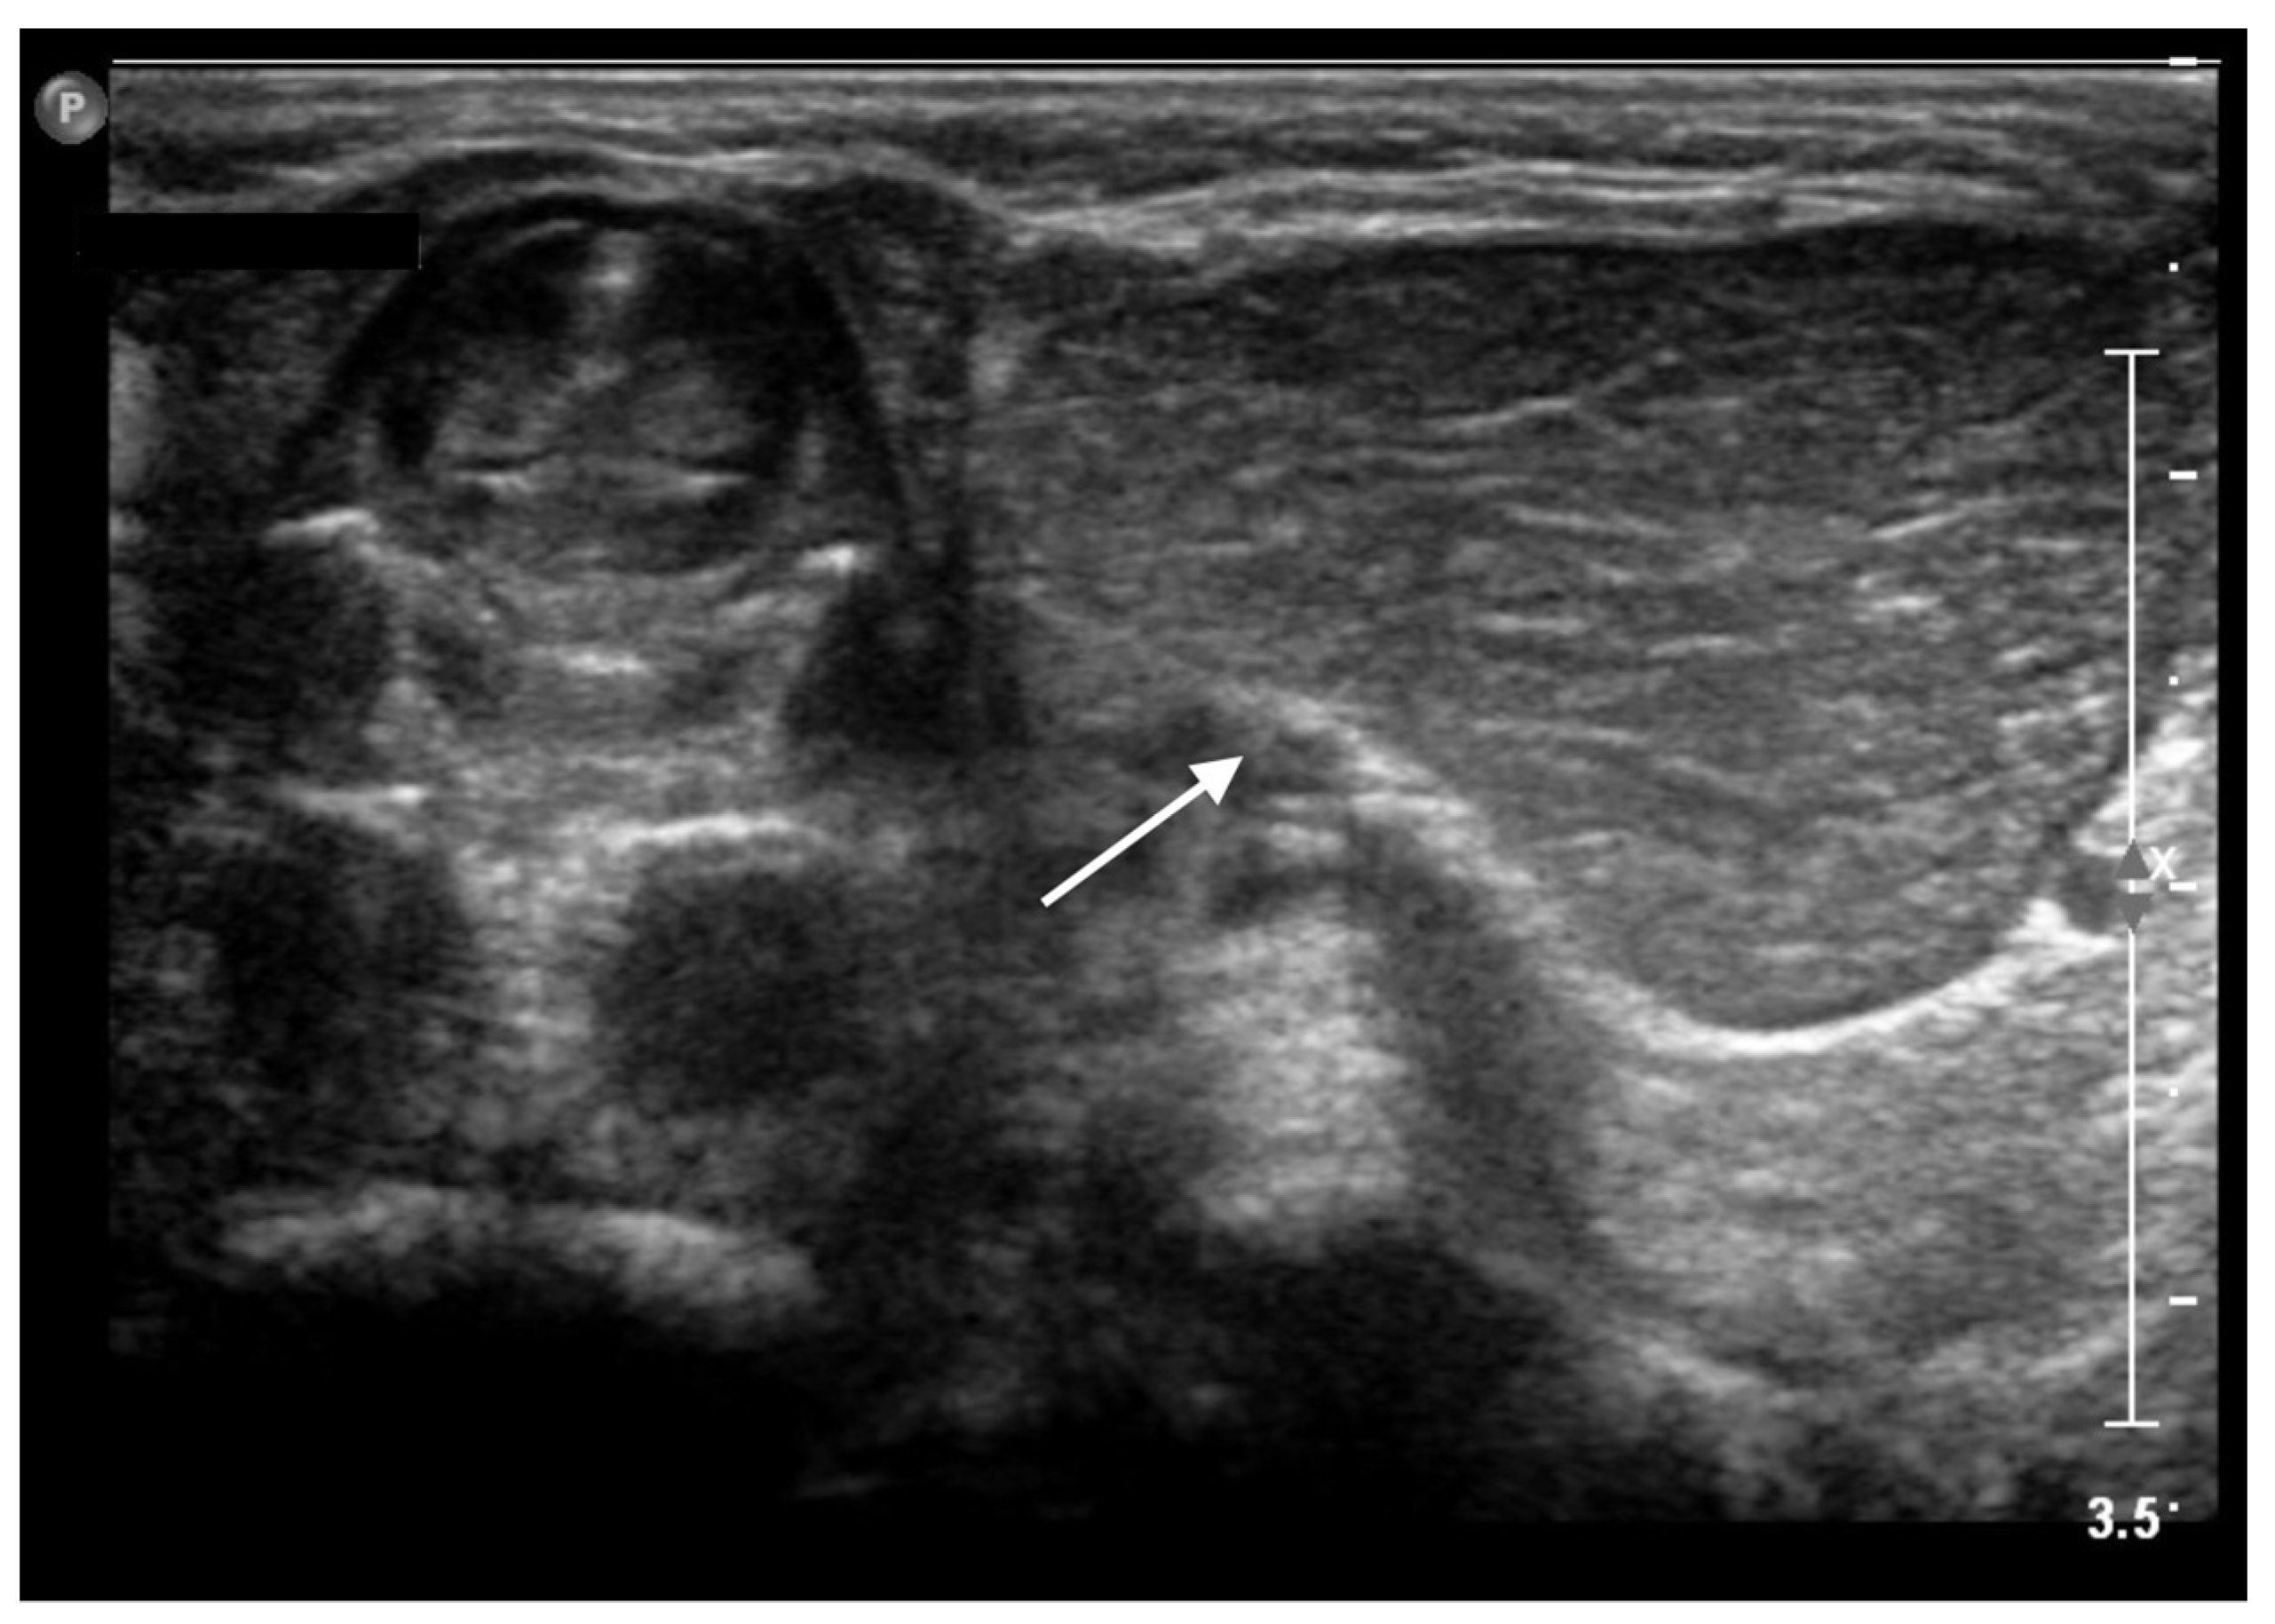

The ultrasound showed a 2 × 3 cm hypoechoic mass with consensual vascular signal, located to the left side of the cervical trachea. It had a relatively homogeneous background echogenicity, with multiple linear hyperechoic septa (Figure 2).

Transverse sonogram showing a 2 × 3 cm hypoechoic mass (white arrow) with linear hyperechoic foci, located to the left side of the cervical trachea.